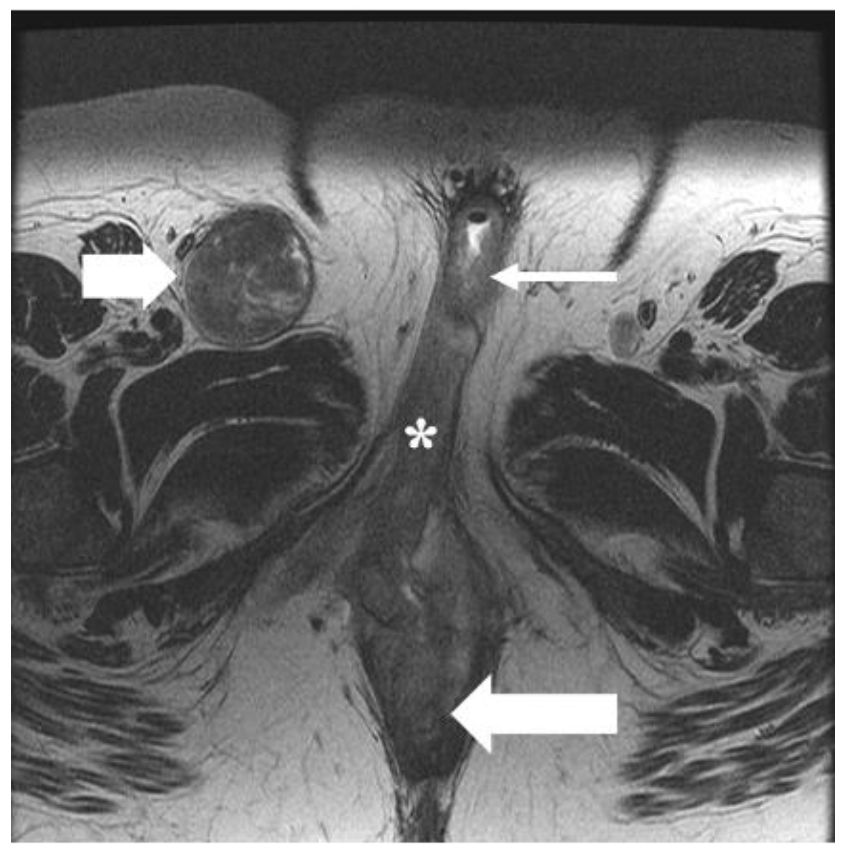

| IV | Tumor of any size fixed to the bone or fixed, ulcerated lymph node metastases, or distant metastases |

| IVA—Disease fixed to the pelvic bone or fixed or ulcerated regional ** lymph node metastases | |